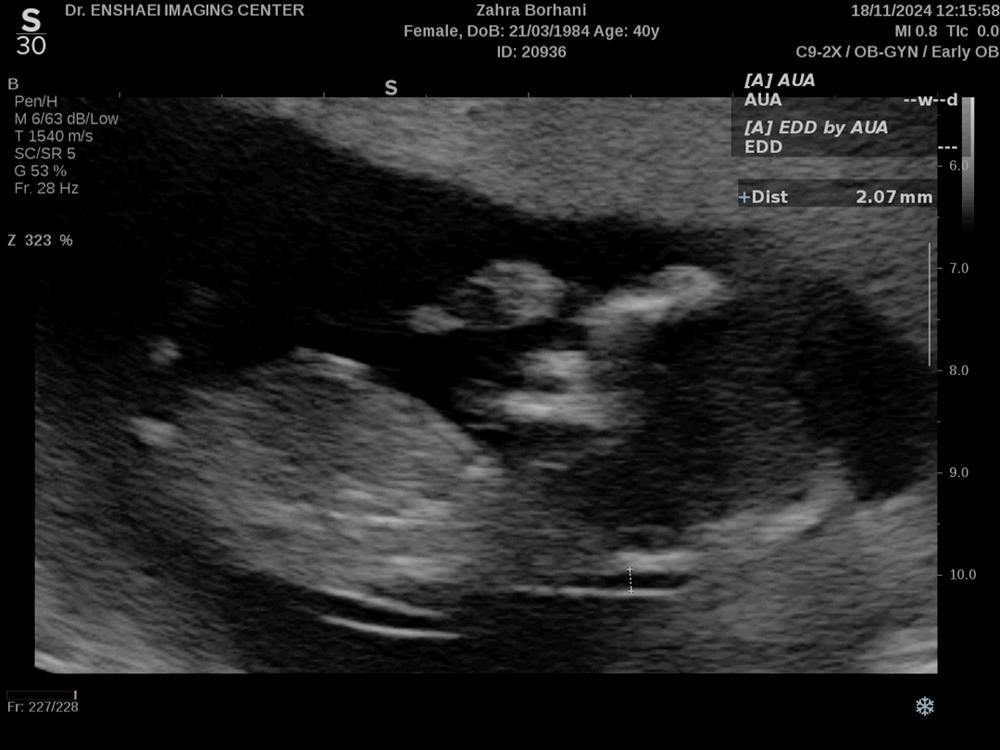

nargiil مدیر استارتر عضویت: 1404/11/25 تعداد پست: 0 عنوان تشخیص جنسیت 36 بازدید | 0 پست کسی میتونه از روی سونوی انتی جنسیت رو تشخیص بده؟ امروز | 11:26 0 نفر لایک کرده اند ... گزارش تاپیک نامناسب